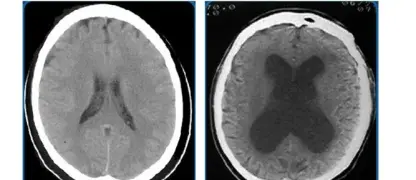

The neurological basis of the movement disorder